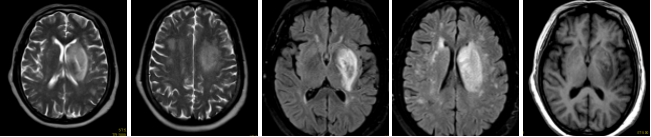

1、中樞神經(jīng)系統(tǒng)

病例一 男,53歲, 突發(fā)右側(cè)肢體力弱, 言語(yǔ)不清, 伴惡心嘔吐、 伴頭暈頭昏、 伴視力模糊, 無(wú) 意識(shí)障礙、 無(wú)面癱。

CBT CBV MTT DLY TTP

從圖中CTA可見(jiàn)左側(cè)大腦中動(dòng)脈M 1段閉塞。

腦灌注所示左側(cè)大腦中動(dòng)脈供血區(qū)DLY、 TTP、 MTT時(shí)間顯著延長(zhǎng),CBF略減低, 考慮為 急性腦梗死; 左側(cè)額葉、 頂枕葉CBF、 CBV顯著減低, 符合軟化灶表現(xiàn)。

經(jīng)大動(dòng)脈腦血管造影+機(jī)械血栓清除+動(dòng)脈內(nèi)溶栓術(shù), 顯示血管病變位置與CTA顯示病變 位置相符, 治療后, 該血管供血區(qū)域得到明顯改善。

核磁共振檢查證實(shí)梗死核心區(qū)域與灌注圖所示區(qū)域匹配。

患者術(shù)后復(fù)查腦血管灌注一站式檢查, 腦血管CTA顯示原閉塞的左側(cè)大 腦 中 動(dòng) 脈M 1段 此 次 顯 影 通 暢 , 局 部 中 度 狹 窄 。 腦 灌 注 分 析 顯 示 左 側(cè) 額 葉 及 頂 枕 葉 軟 化 灶 改 變 , 基 本 同 前 ; 原 左 側(cè) 的 大 腦 中 動(dòng) 脈 供 血 區(qū) 大 面 積 灌 注 異 常 較 前 明 顯 改 善 。2 0 1 8 - 1和 2018 - 5月兩次復(fù)查, 都顯示原堵塞血管通暢, 與溶栓后對(duì)比無(wú)明顯變化。

640層寬體探測(cè)器CT為16 cm覆蓋不動(dòng)床一站式神經(jīng)成像, 通過(guò)一次注藥, 一次掃描可以 獲得完整的純動(dòng)脈期、 純靜脈期和腦血流功能灌注成像及動(dòng)態(tài)CT- DSA電影圖像, 每一個(gè)動(dòng) 態(tài) 數(shù) 據(jù) 都 是 在 同 一 時(shí) 相 獲 得 , 同 時(shí) 包 含 了 解 剖 和 功 能 的 信 息 , 通 過(guò) 對(duì) 神 經(jīng) 一 站 式 的 快 速 分 析, 在60 秒內(nèi)就可以完成急性腦卒中的全面評(píng)估。

不動(dòng)床的采集模式避免了螺旋穿梭式灌注帶來(lái)的全器官不在同一時(shí)相采集、 連續(xù)曝光劑 量大的不足; 獨(dú)有的SVD+算法帶來(lái)精準(zhǔn)的灌注結(jié)果, 結(jié)合獨(dú)有的全顱冠狀位和矢狀位的灌 注圖及血管與灌注融合圖像可以清楚顯示梗塞血管及其造成的低灌注區(qū)域, 帶來(lái)精準(zhǔn)的檢查 結(jié)果。

此外, 機(jī)器同時(shí)搭載了雙空間多模型的AIDR 3 D迭代技術(shù), 使得神經(jīng)一站式檢查的劑量 僅需2 - 3 m Sv,造影劑用量?jī)H需40 ml,有效降低了檢查所需的輻射劑量和造影劑用量, 特別 適合需要多次復(fù)查的患者。